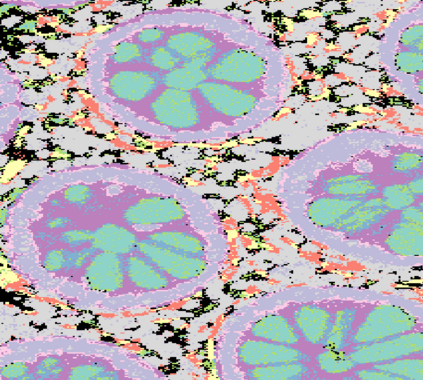

The usage of chemical imaging technologies is becoming a routine accompaniment to traditional methods in pathology. Significant technological advances have developed these next generation techniques to provide rich, spatially resolved, multidimensional chemical images. The rise of digital pathology has significantly enhanced the synergy of these imaging modalities with optical microscopy and immunohistochemistry, enhancing our understanding of the biological mechanisms and progression of diseases. Techniques such as imaging mass cytometry provide labelled multidimensional (multiplex) images of specific components used in conjunction with digital pathology techniques. These powerful techniques generate a wealth of high dimensional data that create significant challenges in data analysis. Unsupervised methods such as clustering are an attractive way to analyse these data, however, they require the selection of parameters such as the number of clusters. Here we propose a methodology to estimate the number of clusters in an automatic data-driven manner using a deep sparse autoencoder to embed the data into a lower dimensional space. We compute the density of regions in the embedded space, the majority of which are empty, enabling the high density regions to be detected as outliers and provide an estimate for the number of clusters. This framework provides a fully unsupervised and data-driven method to analyse multidimensional data. In this work we demonstrate our method using 45 multiplex imaging mass cytometry datasets. Moreover, our model is trained using only one of the datasets and the learned embedding is applied to the remaining 44 images providing an efficient process for data analysis. Finally, we demonstrate the high computational efficiency of our method which is two orders of magnitude faster than estimating via computing the sum squared distances as a function of cluster number.